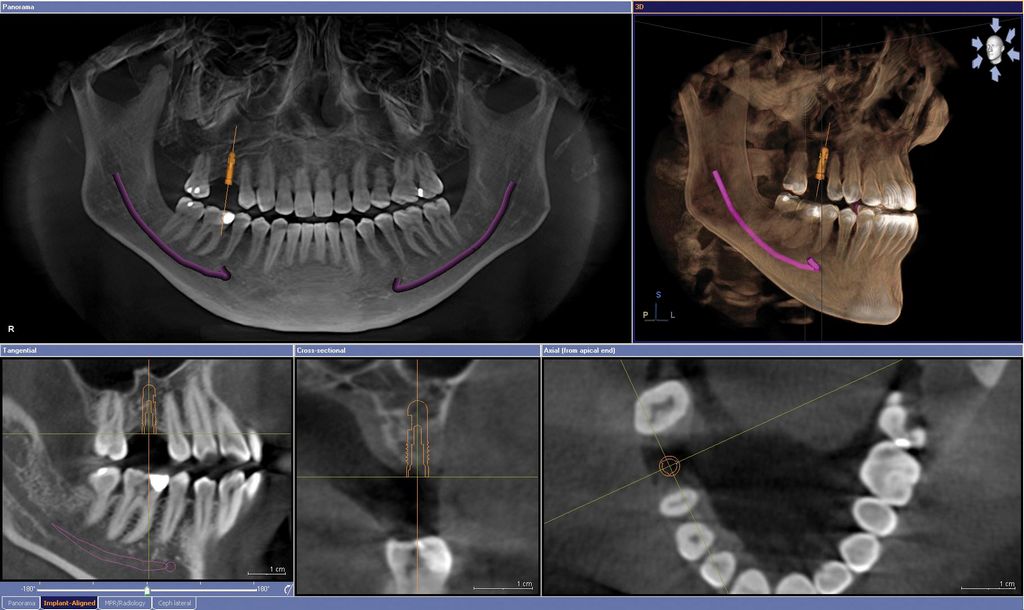

德國Sirona 3D數位電腦斷層掃瞄儀 德國Sirona 3D數位電腦斷層掃瞄儀

本院引進百萬級3D影像系統---全口/側顱/電腦斷層 三合一X光機,為植牙/矯正/根管的最佳選擇,低劑量高解析

(ORTHOPHOS XG 3D Ceph)

可以準確了解牙齒的立體排列情況與根管走向,能確認齒槽骨的型狀及神經,血管的位置。將資訊採入治療計畫內,大幅提升手術成功率。

安全性高-- 確認牙齒位置,可減少組織破壞,傷口更小流血少,疼痛少,腫脹更少。

輻射劑量低--牙科專用電腦斷層劑量低,為傳統醫用電腦斷層的2%。